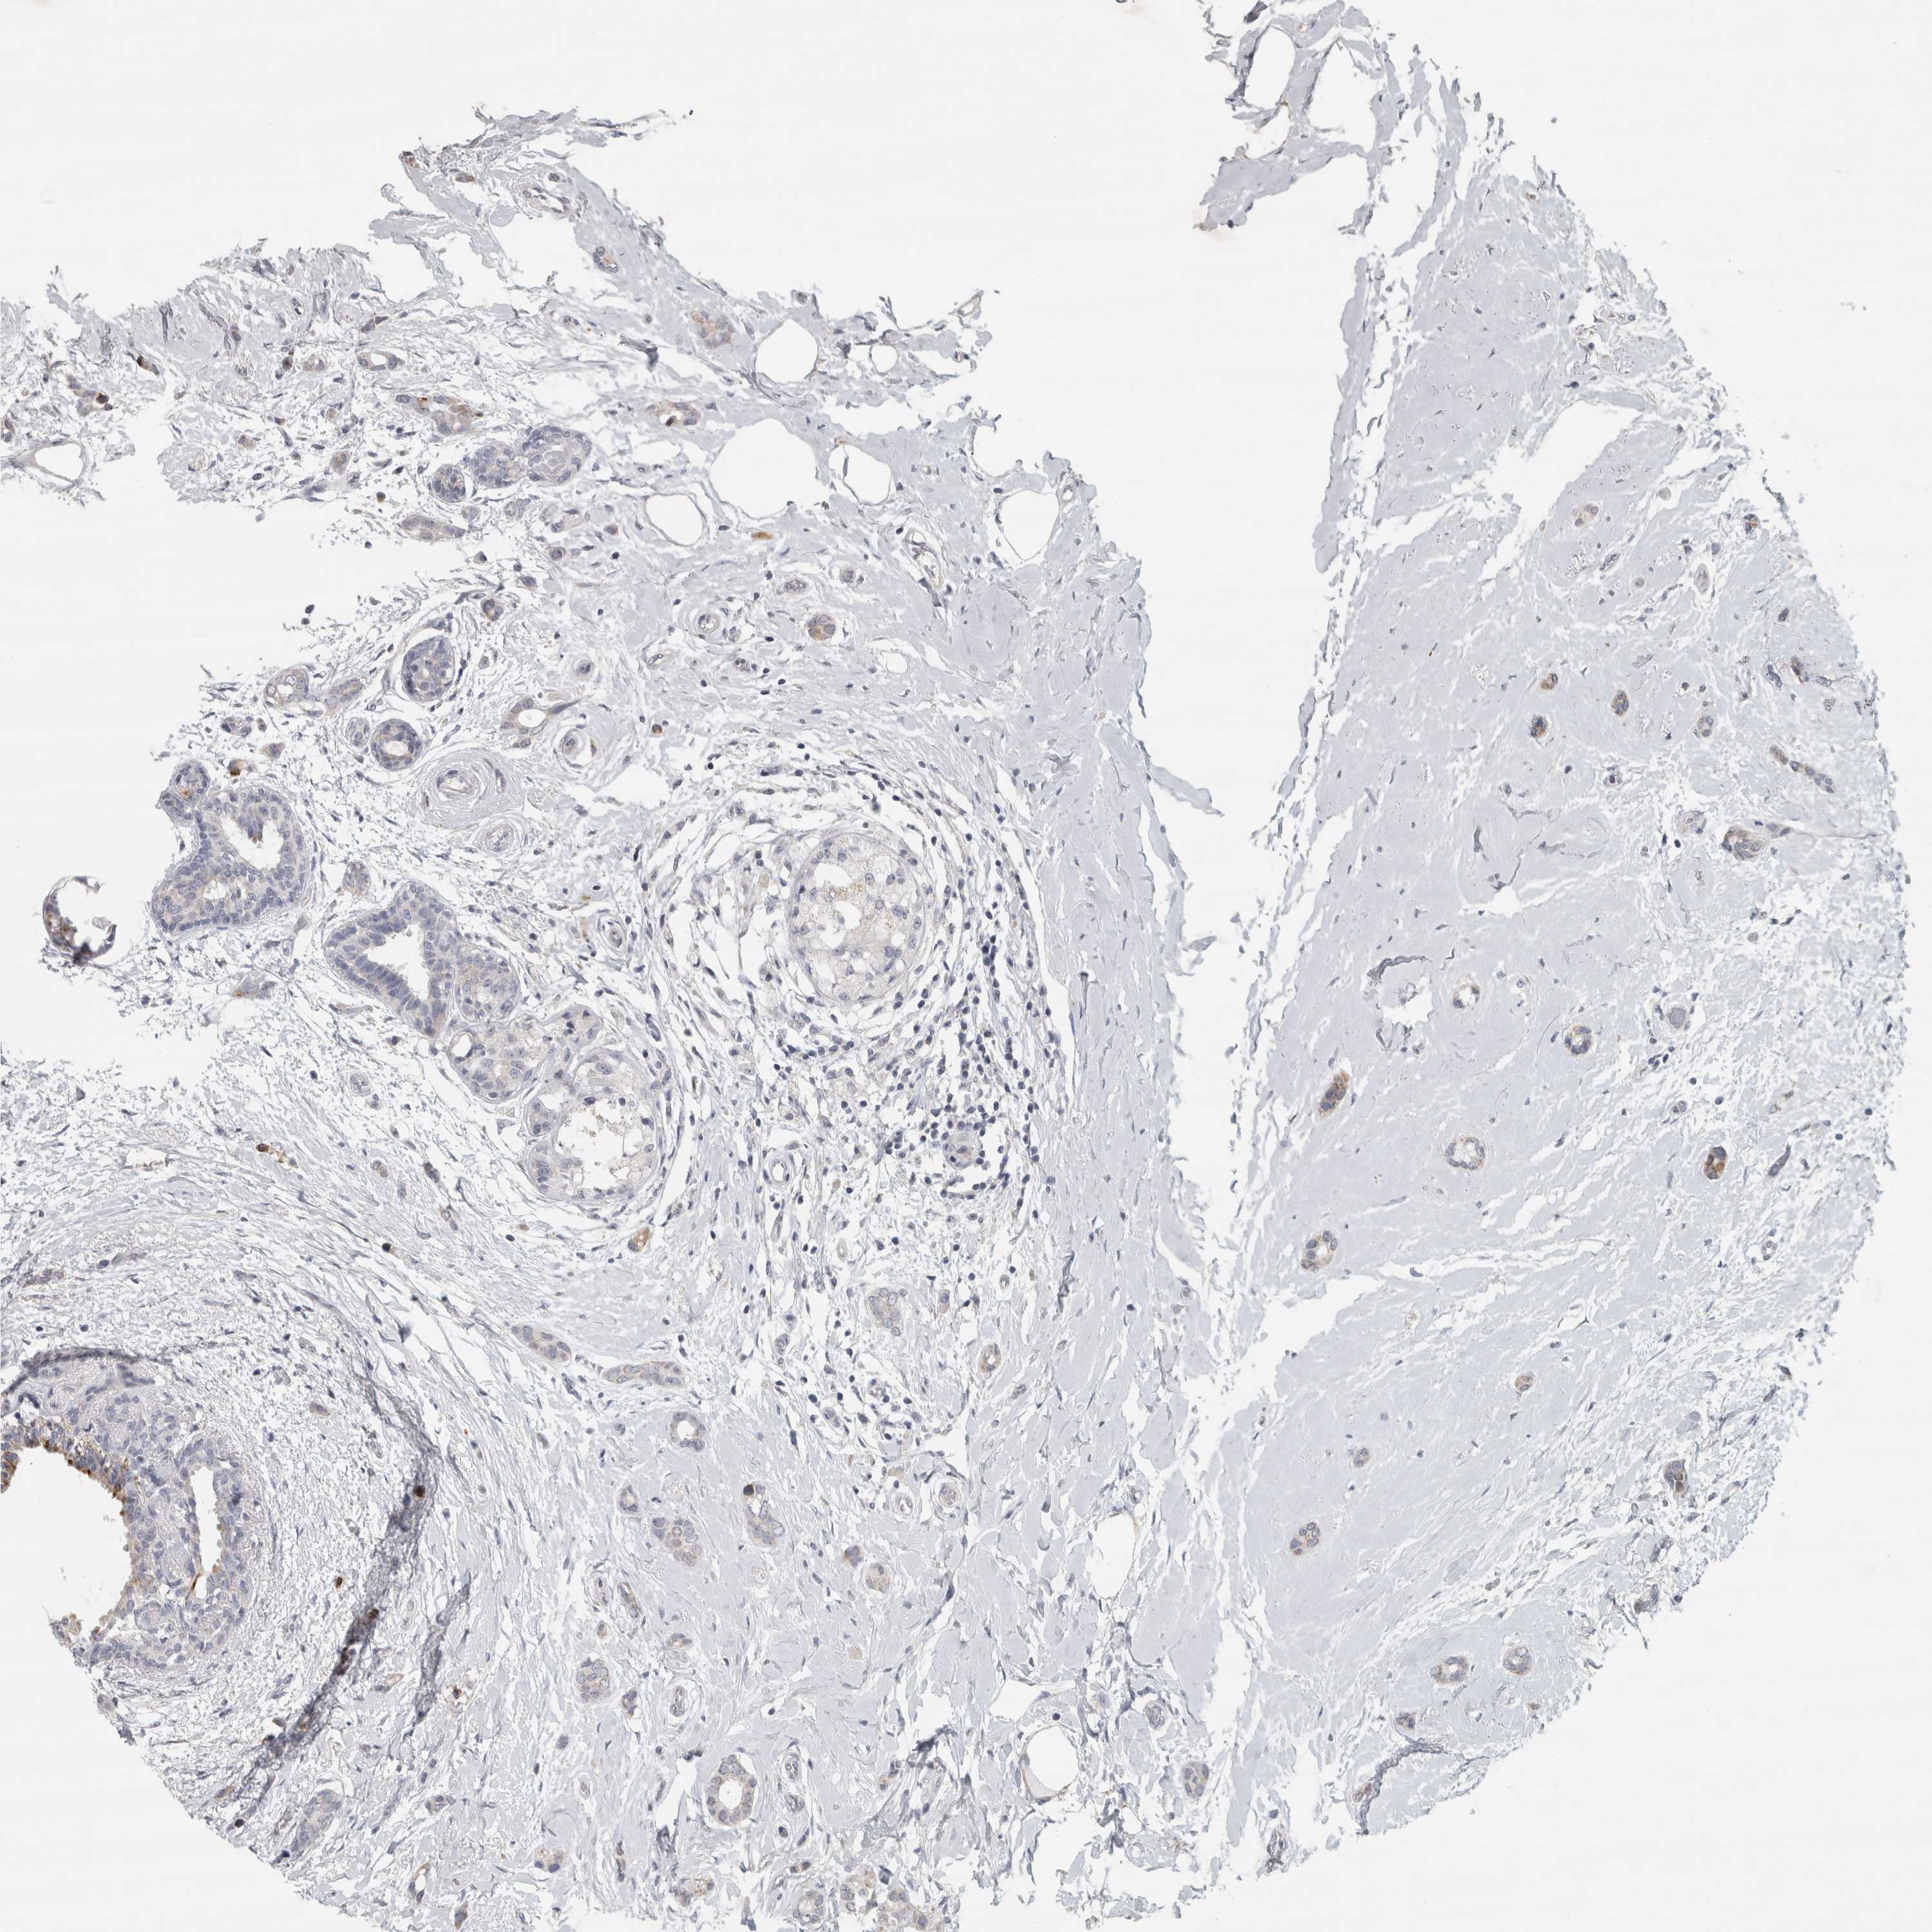

BRCA TCGA BRCA VALIDATION PROTEIN EXPRESSION

ANTIBODIES

AND

VALIDATION